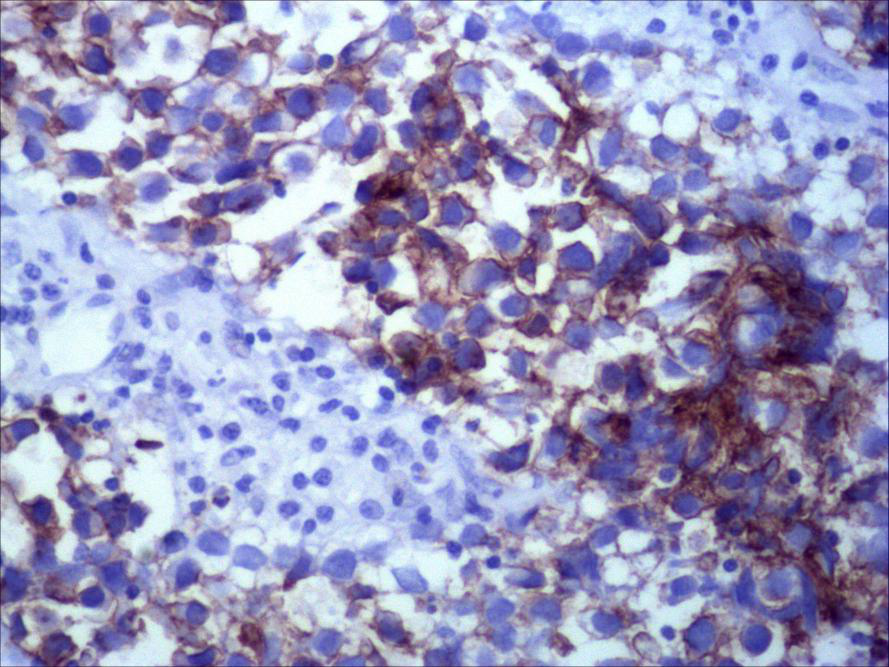

图3:左侧卵巢无性细胞瘤免疫组织化学图片PLAP 200X

后续患者术后恢复良好,并接受了抗肿瘤相关治疗。病理科主任刘晓刚在术后标本病理诊断中也明确诊断(左附件)卵巢无性细胞瘤。后经中国医学科学院肿瘤医院病理科专家会诊,证实此例病理诊断准确,并得到会诊专家的高度表扬。出院前,患者及家属还特意前来病理科,与蔡辉、和时任妇科主任苏光合影留念。